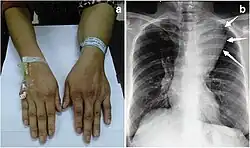

| Large mediastinal angiolipoma | |

Angiolipoma is a subcutaneous nodule with vascular structure, having all other features of a typical lipoma. They are commonly painful.[1]: 624 [2] Angiolipomas manifest as multiple painful subcutaneous nodules commonly on the upper limbs. The can occur sporadically, with a family history or after trauma. Angiolipomas can be seen on CT scans and MRI but are diagnosed based on histopathology. Total excision or liposuction is used to treat angiolipomas. They are more common in men and usually appear in third and second decades of life.

Angiolipoma typically manifests as many, painful subcutaneous nodules (solitary in only one-third of patients), most commonly originating in the upper limbs (of which the forearm accounts for around two thirds), trunk, and lower limbs.[3][4] These lesions are well-defined, usually measuring less than 4 cm.[5]